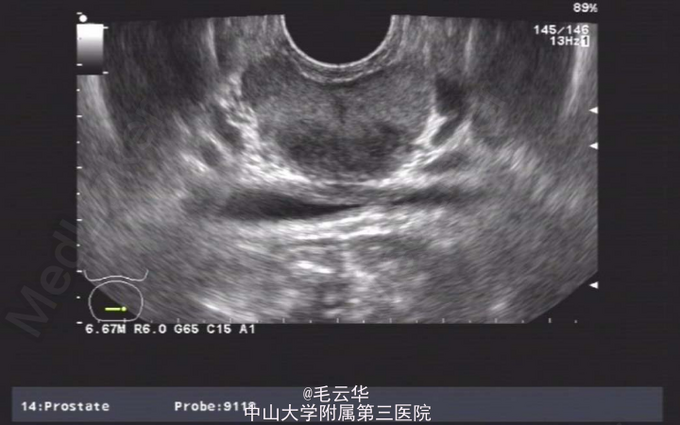

双肾区无红肿、隆起,无叩痛,双侧肋脊点、肋腰点无压痛。腹平软,双侧上中输尿管点无压痛,膀胱区无压痛。双侧腹股沟区未触及肿物,尿道外口未见异常,阴囊无水肿,双睾丸可触及,肛周皮肤无红肿。盆腔MR提示:双侧精囊腺体积缩小(未见片)。彩超提示:右侧输精管、精囊缺如可能;双侧睾丸偏大,附睾小管扩张;前列腺囊肿。精液常规提示精液量少,离心后无精子。

入院诊断:无精症查因。 入院完善术前相关检查,射精管切开+输精管探查术。麻醉成功后,取截石位,常规消毒铺巾,连接好4.5/6.5F输尿管硬镜和监视系统。经尿道进镜入膀胱,见双侧输尿管开口裂隙状,膀胱内未见异常。尿道未见明显异常,精阜稍隆起。镜下未找到双侧射精管开口,硬膜外导管引导进镜入前列腺小囊,见囊腔狭小,囊壁炎性增厚,囊内未见射精管开口,考虑射精管口梗阻,遂换用电切镜,切除部分精阜,切开双侧射精管口,再用硬膜外导管引导输尿管硬镜入射精管,进入困难,结合病史及影像学检查,提示射精管发育不良并梗阻。作双侧阴囊切口,逐层切开,游离出睾丸和精索,探查双侧输精管,见左侧输精管呈纤维条索状,未见管腔结构,右侧未见输精管,考虑为先天缺如,遂行双侧睾丸活检,术野予以止血,逐层缝合切口,术毕。手术过程顺利,麻醉效果满意,术中无出血,术后安返病房。